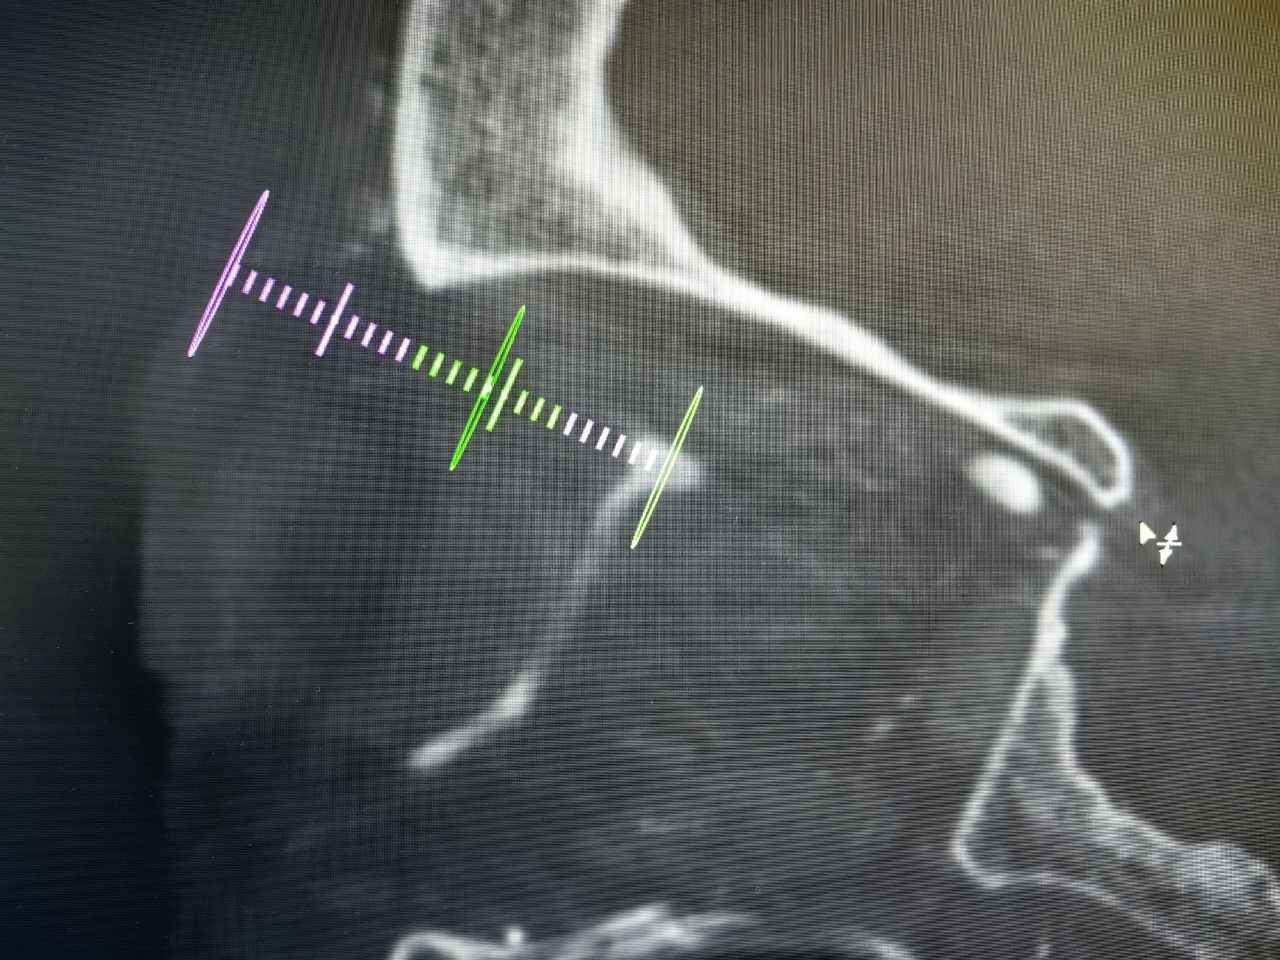

Выбранный путь проходил через верхнюю глазничную щель, рядом с такими важными структурами, как глазной, глазодвигательный блоковый и отводящий нервы. Благодаря возможностям современного ангиографа врач обеспечил себе навигацию в таких сложных условиях и определил оптимальную траекторию. Контрольные снимки после имплантации спиралей и эмболизата подтвердили, что фистула полностью выключена из кровотока.